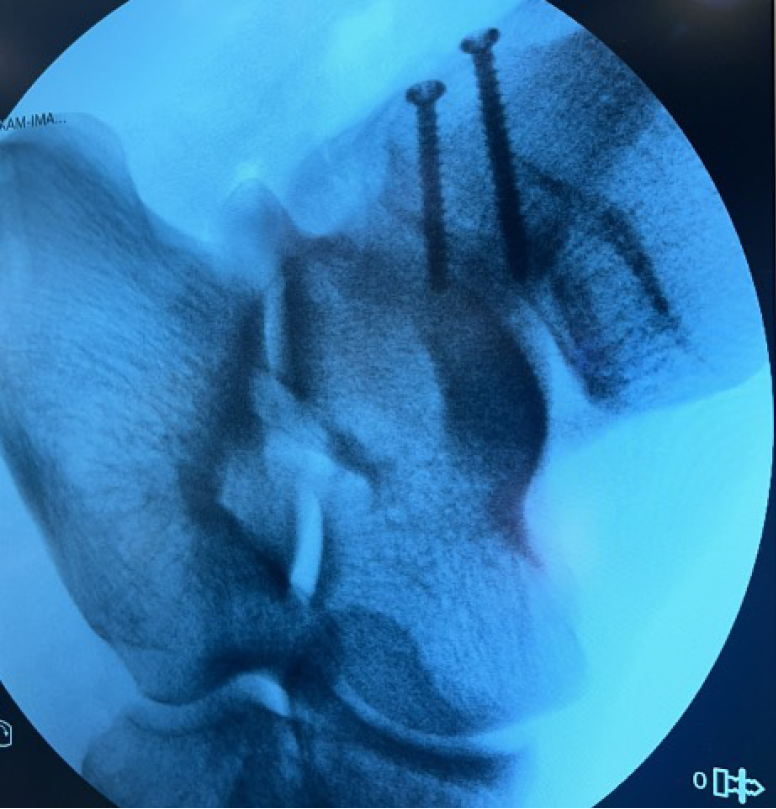

Figure 4 Intraoperative lateral fluoroscopic view of the ankle demonstrates distal fibula fracture reduced and fixated with two 3.

0 mm lag screws.